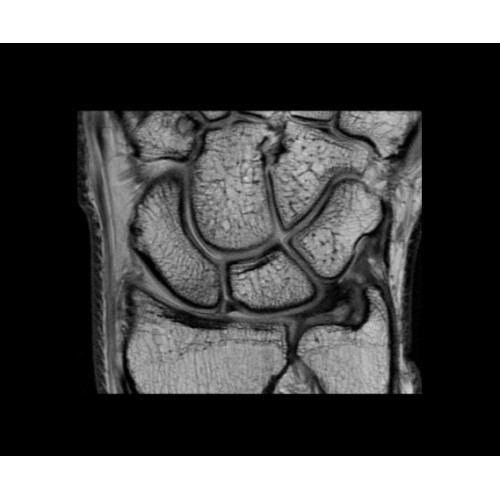

В систему SIGNA PET/MR встроены запатентованные детекторы кремниевого фотоумножителя (SiPM) и сверхчувствительные кристаллические сцинтилляторы на основе лютеция толщиной 25 мм. Благодаря этому обеспечивается исключительная чувствительность и возможность использования времяпролетной диагностики (TOF).

Кроме того, в результате использования технологии TOF и инновационной технологии реконструкции Q.Clear вы сможете добиться прекрасного соотношения сигнал/шум. А благодаря технологии нулевого времени эхо (ZTE) визуализировать костную структуру без ионизирующего излучения. Все эти разработки для улучшения качества сканирования и точности анализа помогут вам использовать весь потенциал ПЭТ/МРТ.

• Современные кристаллический сцинтилляторы на основе лютеция (LBS) с усовершенствованными спектральными отражателями (ESR).

• Кремниевые фотоэлектронные умножители (SiФЭУ).